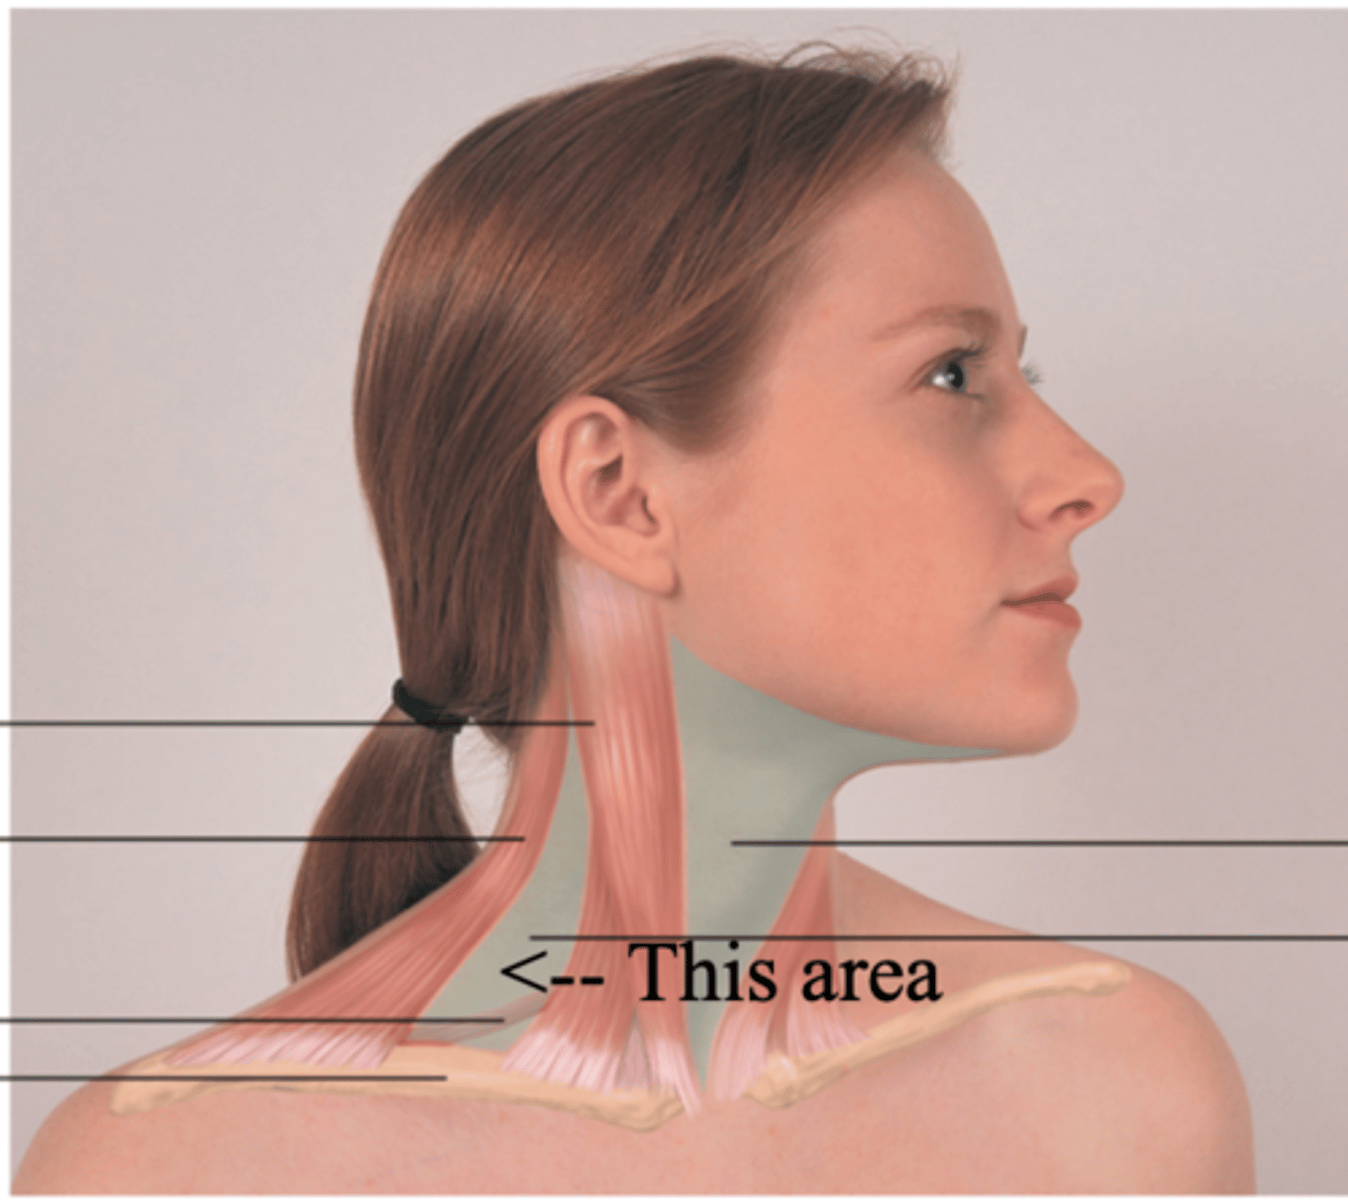

Anterior Triangle

The area that lies in front, between the sternomastoid and the midline of the body, with its base up along the lower border of the mandible and its apex down at the suprasternal notch

Posterior Triangle

The area of the neck between the sternocleidomastoid muscle and trapezius muscles

Functions of the Neck

- Continuation of the digestive and respiratory system

- Support the passage for many structures to and from the brain